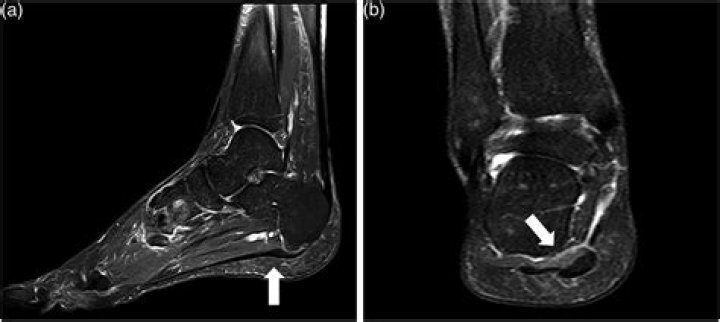

MRI (Magnetic Resonance Imaging)

MRIs can pinpoint plantar tears or ruptures, tendon injuries, lesions, cysts, and sometimes fractures or heel spurs, without the radiation and expense of a CT-scan. MRIs are also sometimes used to confirm Haglund's Deformity and Achilles tendonitis.